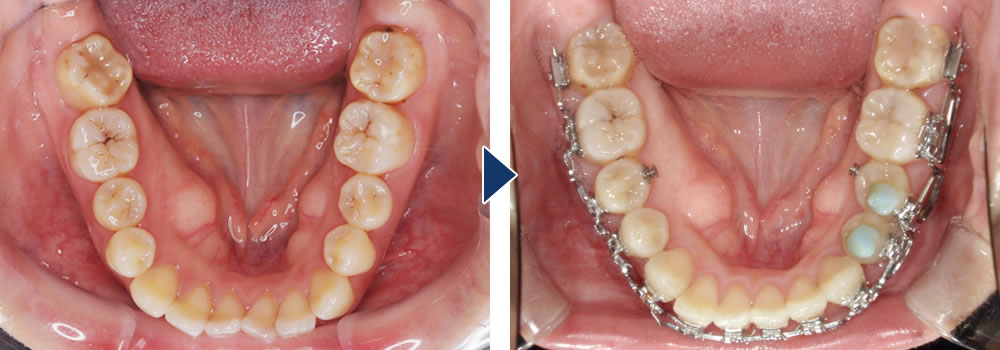

MEAW矯正の最大の利点は1本1本の歯を自由な方向に力をかけることができるところです。例えば、小臼歯で捻転してしまっている歯を回転させるのは、難しいとされていますが、MEAW矯正では比較的容易です。

歯列を広げることで本来、抜歯が必要な症例でも歯を並べることが出来ることがあります。